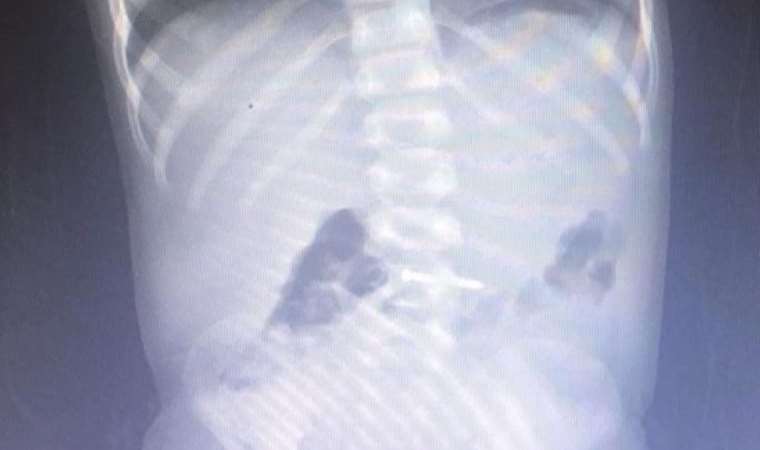

Bu rahatsızlıkları yaşayan 65 öğrenci Uşak Eğitim ve Araştırma Hastanesi ve kentteki bir özel hastanede tedaviye alındı. Tedavileri tamamlanan 32 öğrenci taburcu edildi.

Ergün şu ana kadar toplam 65 öğrencinin hastanelere müracaat ettiğini belirterek "32'si serum verilerek taburcu edildi. 3 hastamız yatarak tedavi ediliyor. Onların da sağlık durumları iyi. Bizi sevindiren olay şu, Allah'a şükür hayati tehlikesi olan yok. Olayla ilgili adli soruşturmayı, biz de Valilik olarak idari soruşturmayı başlatıyoruz. Kamuoyuyla da sonuçları paylaşacağız" dedi.